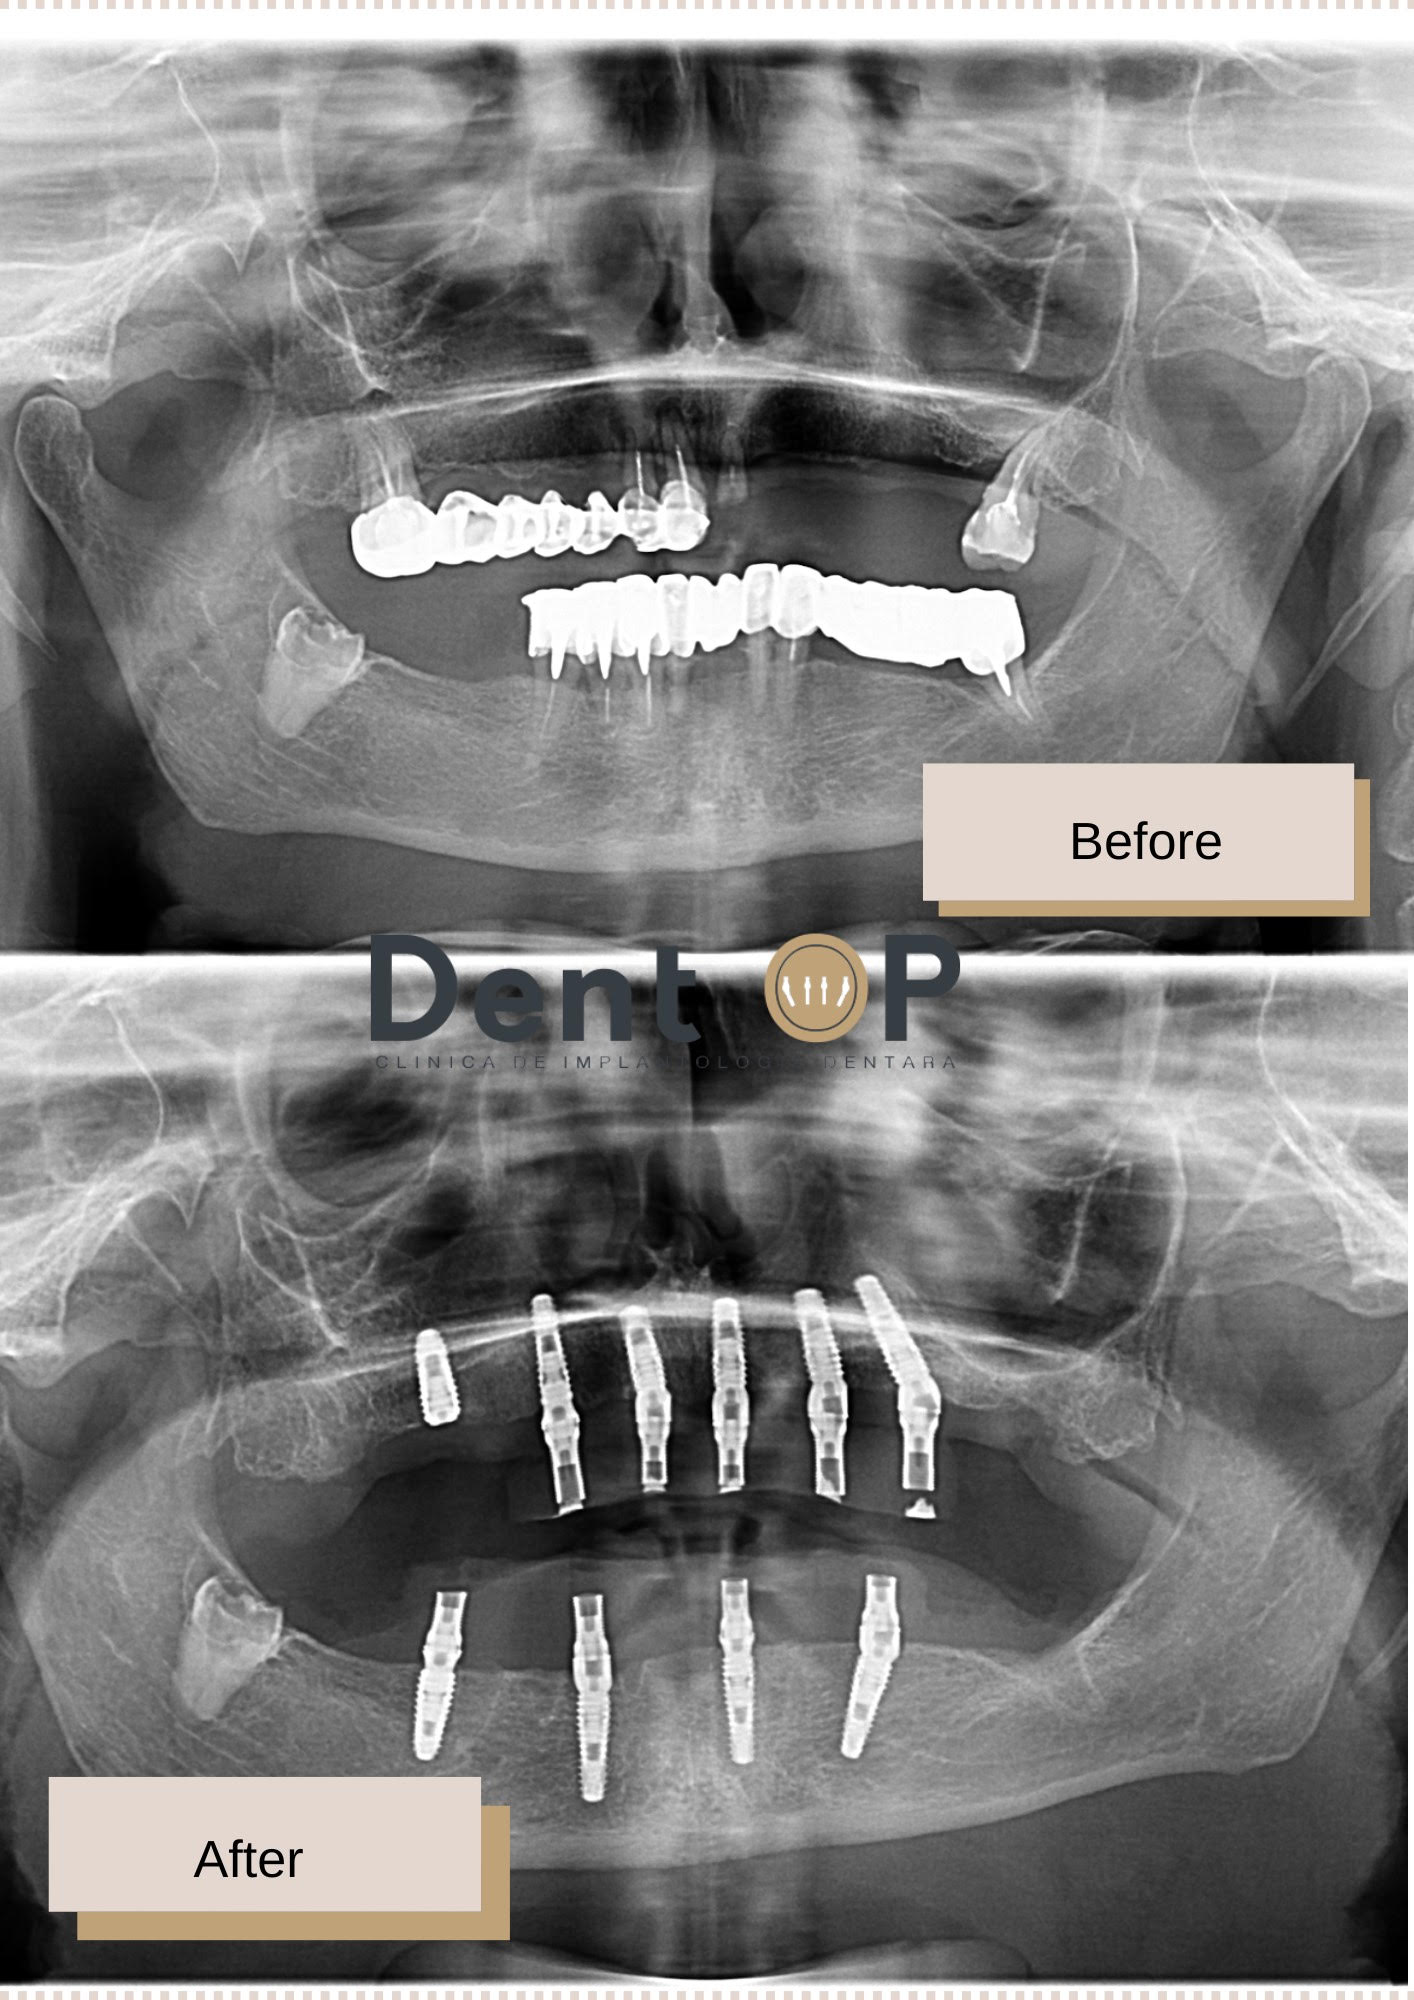

Doamna N. a venit la noi pentru o evaluare dentară de specialitate și astfel a decis că soluția cu implanturi dentare este potrivită cazuluisău clinic. În cadrul consultației i-a fost efectuată o radiografie panoramică, iar Dr Cazacu Corrado i-a propus inserarera a 10 implanturi dentare dintre care 6 la maxilar și 4 la mandibulă, inserate în două intervenții diferite.

Există cazuri în care pacienții aleg inserarea implanturilor dentare în două etape, astfel ei consideră că intervenția va fi mai rapidă. Recomandăm rezolvarea problemelor care nu mai suportă așteptare acolo unde este cazul, iar astfel am putut proceda și cu pacienta în cauză. În cadrul primei intervenții i-au fost inserate la maxilar 6 implanturi dentare, iar în cea de-a două intervenție, 4 implanturi dentare, ambele cu ajutorul Sedării Conștiente.

În doar 24h de la cele două intervenții, pacienta a primit pe rând lucrările provizorii, astfel ea nu a stat fără dantură după extragerea lucrărilor vechi. Pe perioada de 4-6 luni în etapa lucrărilor provicorii, pacienta a avut o dietă semi-lichidă și s-a prezentat periodic la clinică pentru monitorizarea evoluției implanturilor dentare și a vindecării.